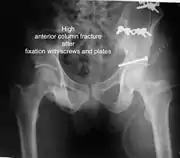

Anterior columnThis fracture is uncommon, typically occurring when the injuring force is applied from the side, against the greater trochanter of the femur bone, as in a fall on the side or being hit on the side. Depending on the location, the fractures are described as very low, low, intermediate and high anterior column fracture. Anterior column + posterior hemi transverseIn this variety of fractures, the posterior or ilio ischial column is broken as a transverse fracture, while the anterior or ilio pubic column is broken into multiple pieces. Part of the weight-bearing dome in this variety of fractures is still attached to that part of the iliac wing, which forms part of the iliac joint. This type of injury has to be differentiated from both column fractures, where the weight-bearing dome is a floating piece not attached directly to the bone-forming sacroiliac joint.

Typically, it is caused by a combination of forces acting on the hip through the femoral head. All three X-ray views plus a CT scan are a must for the diagnosis and management of this complex injury. In this injury, non-operative treatment rarely gives satisfactory results. Surgical management is ideal. The choice of approach rests with the surgeon but going from the front or anterior approach is necessary. The posterior injury may be tacked with the anterior approach by an experienced surgeon. If the patient is unfit to undergo major surgery due to any reason, longitudinal traction to achieve secondary congruence of the hip may help to restore hip function, though partially.

The final management depends on the size of the fragment(s), stability and congruence of the joint. In some cases traction for six to eight weeks may be the only treatment required; however, surgical fixation using screw(s) and plate(s) may be required if the injury is more complex. The latter treatment will be called for if bone fragments do not fall into place, or if they are found in the joint, or if the joint itself is unstable.